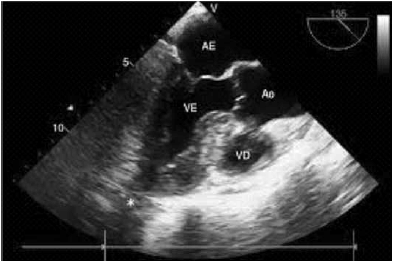

Paciente do sexo feminino, 72 anos, portadora de mieloma múltiplo em investigação atual. Com internação via pronto-socorro, após terceira ida nos últimos meses, pela mesma história de tosse seca, dispneia ao repouso e edema de membros inferiores. Ao exame físico, apresenta hipofonese de bulhas e presença de terceira bulha, com queda da pressão arterial sistólica de 15 mmHg durante a inspiração profunda; estertores crepitantes nos dois terços inferiores dos pulmões. O eletrocardiograma de repouso com padrão de baixa voltagem e sem sinais de sobrecarga de câmaras esquerdas e o ecocardiograma realizado à beira a leito, na UTI, é o que segue:

A etologia que deve ser pesquisada para o quadro clínico?